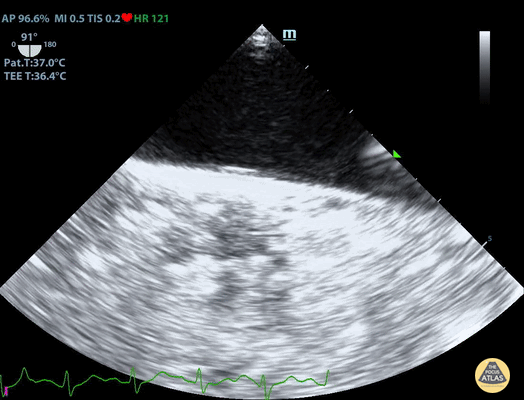

TEE Normal Aorta Long Axis Duncan McGuire, DO, Emergency Medicine, Beaumont Health

https://www.thepocusatlas.com/tee